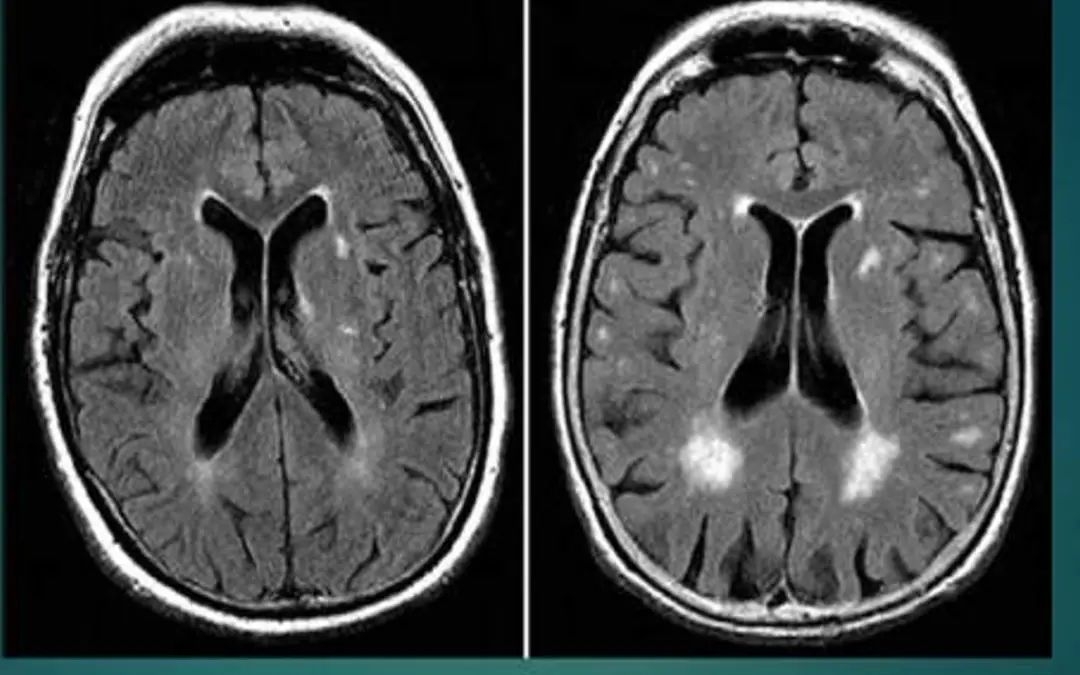

脑白质脱髓鞘

表现为皮层下白质及侧脑室周围多发点状或斑片状长Tl、长T2信号,可以与其他类型影像学损害并存。临床表现为精神障碍、行走困难、肌张力高、病理征阳性等。

以上影像学改变可单独亦可多种共存。